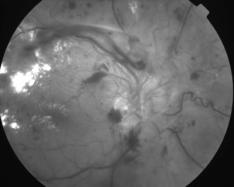

IMG0002.JPG